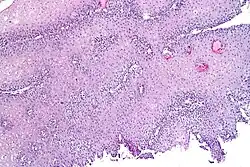

Histopathology of GERD

Esophageus with moderate GERD showing dilatation of intercellular spaces

Nerve endings and acid-sensitive ion channels in the deepest layer of the esophagus are usually protected by anatomical barriers. However, in gastroesophageal reflux disease (GERD), one of the earliest signs of damage is the development of dilated intercellular spaces (DISs) in the esophageal lining. These spaces weaken the protective barrier, allowing acid and other substances to seep in.[13][11] This triggers pain-sensitive nerves, which send signals to the brain and cause the sensation of heartburn.[11][14]